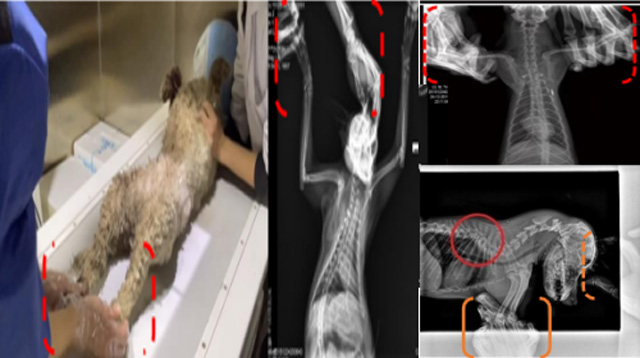

現(xiàn)在寵物醫(yī)療設(shè)備得到高速發(fā)展,現(xiàn)在有越來(lái)越多的寵物診療機(jī)構(gòu)配置X射線裝置如寵物DR。寵物骨折或者有其他疾病不能通過(guò)直觀看出來(lái)的。寵物診所醫(yī)生都會(huì)使用寵物DR來(lái)做輔助檢查。但是有時(shí)候?qū)櫸镝t(yī)生沒(méi)有加強(qiáng)防護(hù),就在寵物DR室給寵物拍X片做檢查。這樣也是會(huì)受到X射線的輻射。因?yàn)閄射線上崗是屬于職業(yè)病危害崗位。長(zhǎng)期的輻射會(huì)對(duì)人體造成一定的危害。寵物醫(yī)生也需要接受X射線照射的上崗前都必須進(jìn)行放射工作人員的職業(yè)健康體檢。體檢不合格的話是不能擔(dān)任放射工作的。未經(jīng)上崗前職業(yè)健康體檢的勞動(dòng)者從事接觸職業(yè)病危害作業(yè)的行為,已經(jīng)違反了《中華人民共和國(guó)職業(yè)病防治法》第三十五條規(guī)定,依據(jù)《中華人民共和國(guó)職業(yè)病防治法》第七十五條規(guī)定,需要進(jìn)行整改罰款。開(kāi)展寵物放射診療活動(dòng),在日常工作中,對(duì)本機(jī)構(gòu)的X射線危害的職業(yè)病防治,需要知道并做到以下內(nèi)容: